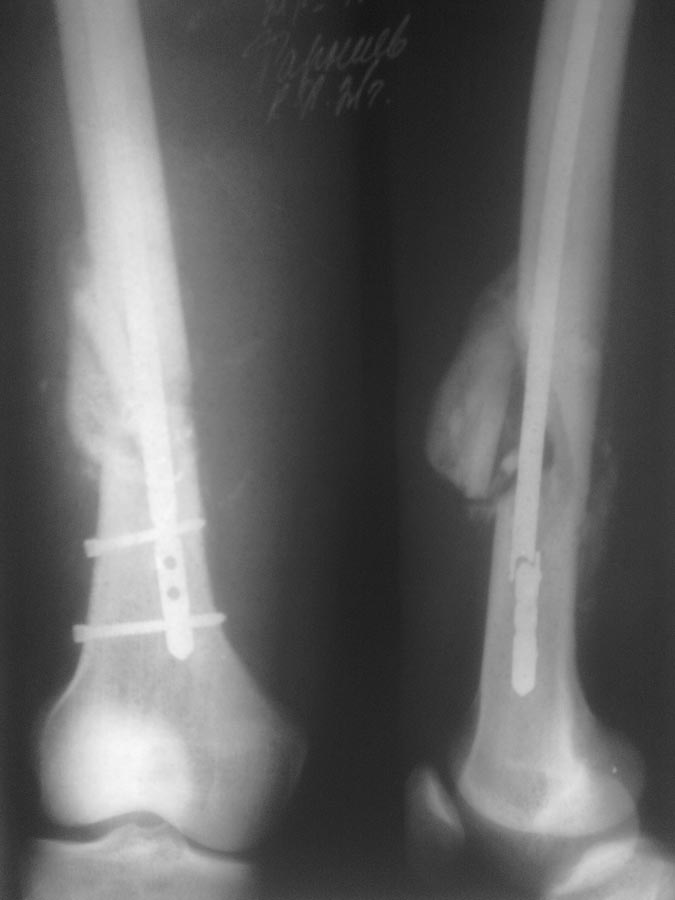

> Пациенту ровно полтора месяца назад проводилось оперативное лечение

> оскольчатого перелома н/3 бедренной кости БИОС.

> Гвоздь No. 9. Антеградно. Место перелома не открывалось. Возраст пациента

> 21г. Со слов нагрузку давал не более 30 проц. от веса тела с четвертой

> недели. На 45 день гвоздь ломается, неосторожно перевернулся в кровати.

> Вопрос: что делать? Заранее спасибо!

После удаления, пожалуй, реостеосинтез антеградным толстым длинным штифтом

с рассверливанием с блокированием в дистальном отломке как во фронтальной,

так и в сагиттальной плоскости.